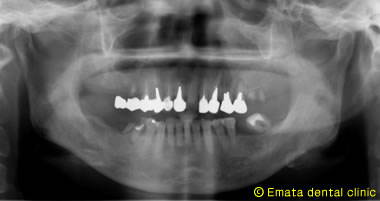

昨日は上顎(上あご)左右2本ずつ4本インプラントを埋入しました。

患者さんはできるだけ早くインプラントの手術を終わらせたいとの(期間と回数)希望でした。

手術時間は約1時間ですが、静脈内鎮静法を行ったので患者さんはオペ終了までほとんど何も覚えてらっしゃらないのでとても楽でした。3週間前に下顎(下あご)を左右同時に4本埋入したので1ヶ月で上下左右8本のインプラントの手術を終えました。

しかし歯周病の初期治療には2ヶ月かかりました。インプラント治療を成功させるためには歯周病の問題を解決しないといけませんね。

術後のレントゲン |